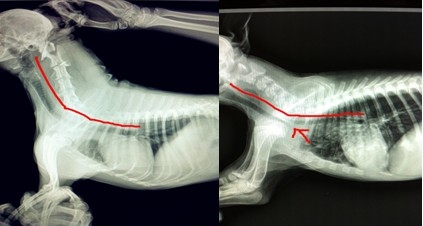

如果您的愛犬依然還是不愿出門,走路會停下休息,那么請仔細往下看。如果您的愛犬還小,雖然喜歡在夏天出門,但是半途會趴下休息,或者喘氣比其他小狗要時間久,那么很有可能是我們說的第一類潛在疾病!氣管類疾病!由于是不種品種的犬種身體結構特征不同,患此類疾病極有品種傾向,常見的有京巴犬,博美犬,吉娃娃犬,斗牛犬,特別是各種品種犬的迷你種,這些犬類常有前天性的氣管疾病,比如氣管狹窄,氣管塌陷。這些小狗平時的表現常有有喜靜不喜動,即使是3歲以內的精力旺盛的年輕犬他們好像也不喜歡奔跑,激動時有類似人類哮喘的病狀,但是安靜一段時間以后就會好了,如果是這樣的話,請你帶上你的愛犬去醫院就診,可以照個X光片,醫生會發現問題的所在。雖然平時這類疾病不會影響您愛犬的生活,但是建議您應該減少夏天的遛狗時間,減少您愛犬的不適。

X光數碼片